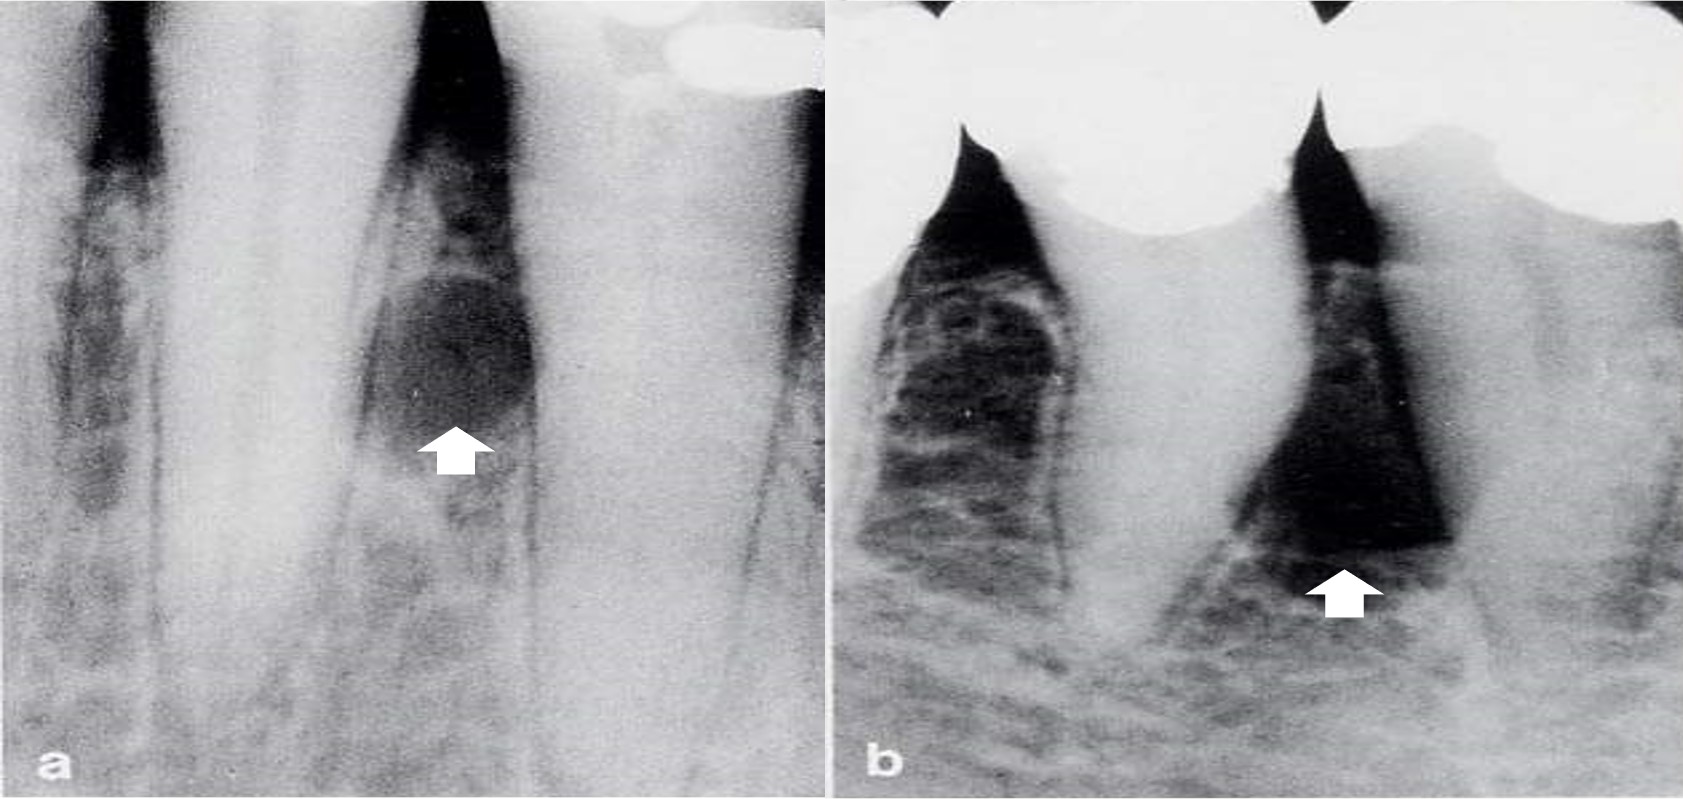

1)临床表现:

多见于20~49岁,男性多见,60%发生于上颌,以上颌切牙和单尖牙最为多见,伴有死髓牙,X线显示圆形或卵圆形透射区,边缘整齐,界限清晰(图13.1-13)。

图13.1-13 根尖周囊肿(X线)

光镜下:囊壁内层由无角化复层鳞状上皮构成,呈网状增生,厚薄不一,部分区域上皮缺如,伴有大量的炎细胞浸润(图13.1-14)。囊腔和囊壁内有胆固醇晶体沉积,呈针状裂隙(图13.1-15),裂隙周边伴有多核巨细胞反应。衬里上皮内可见透明小体(图13.1-16)。透明小体为弓形线状或环状的均质性小体,呈嗜伊红紫色,可位于衬里上皮和纤维囊壁内。